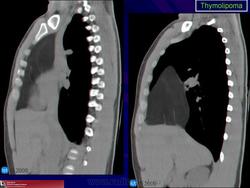

Тимолипома. Как подойти к диагностике? Судя по представленным снимкам, если neo преимущественно жировой структуры локализуется типично для тимомы в переневерхнем средостении + протяженность, объем neo большие и neo выглядит цельным образованием, не составляющими-фрагментами.